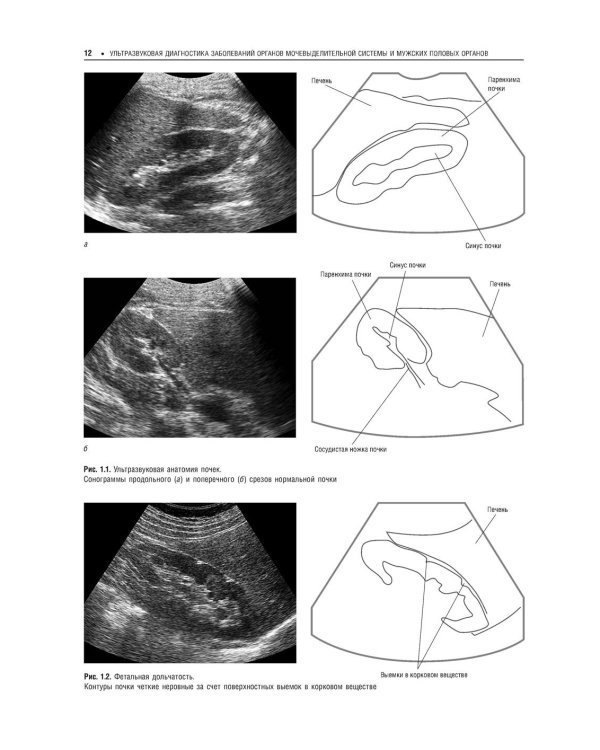

Второй том руководства рассказывает о применении различных методик ультразвукового исследования в диагностике заболеваний почек, мочеточников, мочевого пузыря и мочеиспускательного канала, мужских половых органов и надпочечников. Описывается нормальная ультразвуковая анатомия соответствующих органов, клиника и УЗ-семиотика наиболее часто встречающихся заболеваний и патологий. Отдельная глава посвящена неотложной УЗ-диагностике при острых заболеваниях и повреждениях мочевых органов. Издание адресовано слушателям, обучающимся в системе послевузовского профессионального дополнительного образования, а также специалистам по лучевой диагностике, врачам, работающим в кабинетах и отделениях ультразвуковой диагностики.